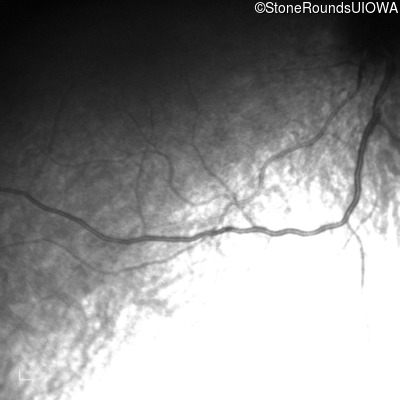

Infrared Fundus Photograph - Right - No Light Perception

Exemplar